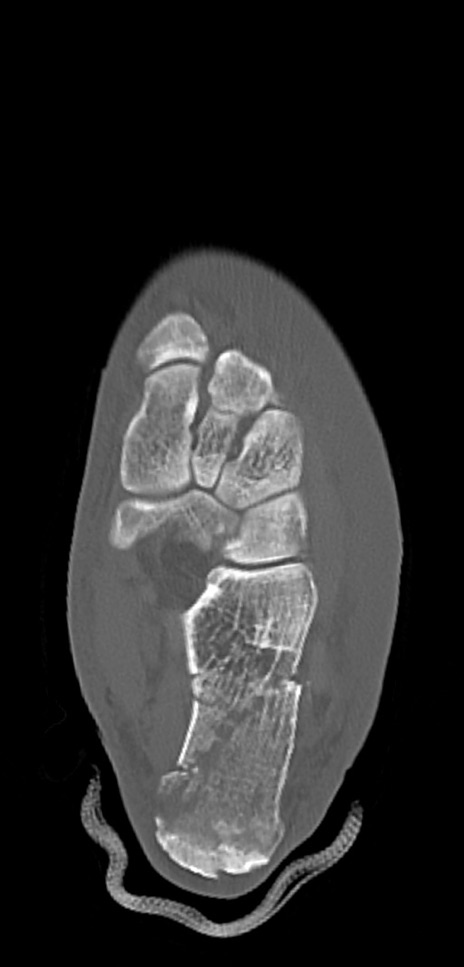

左足関節CT

矢状断像